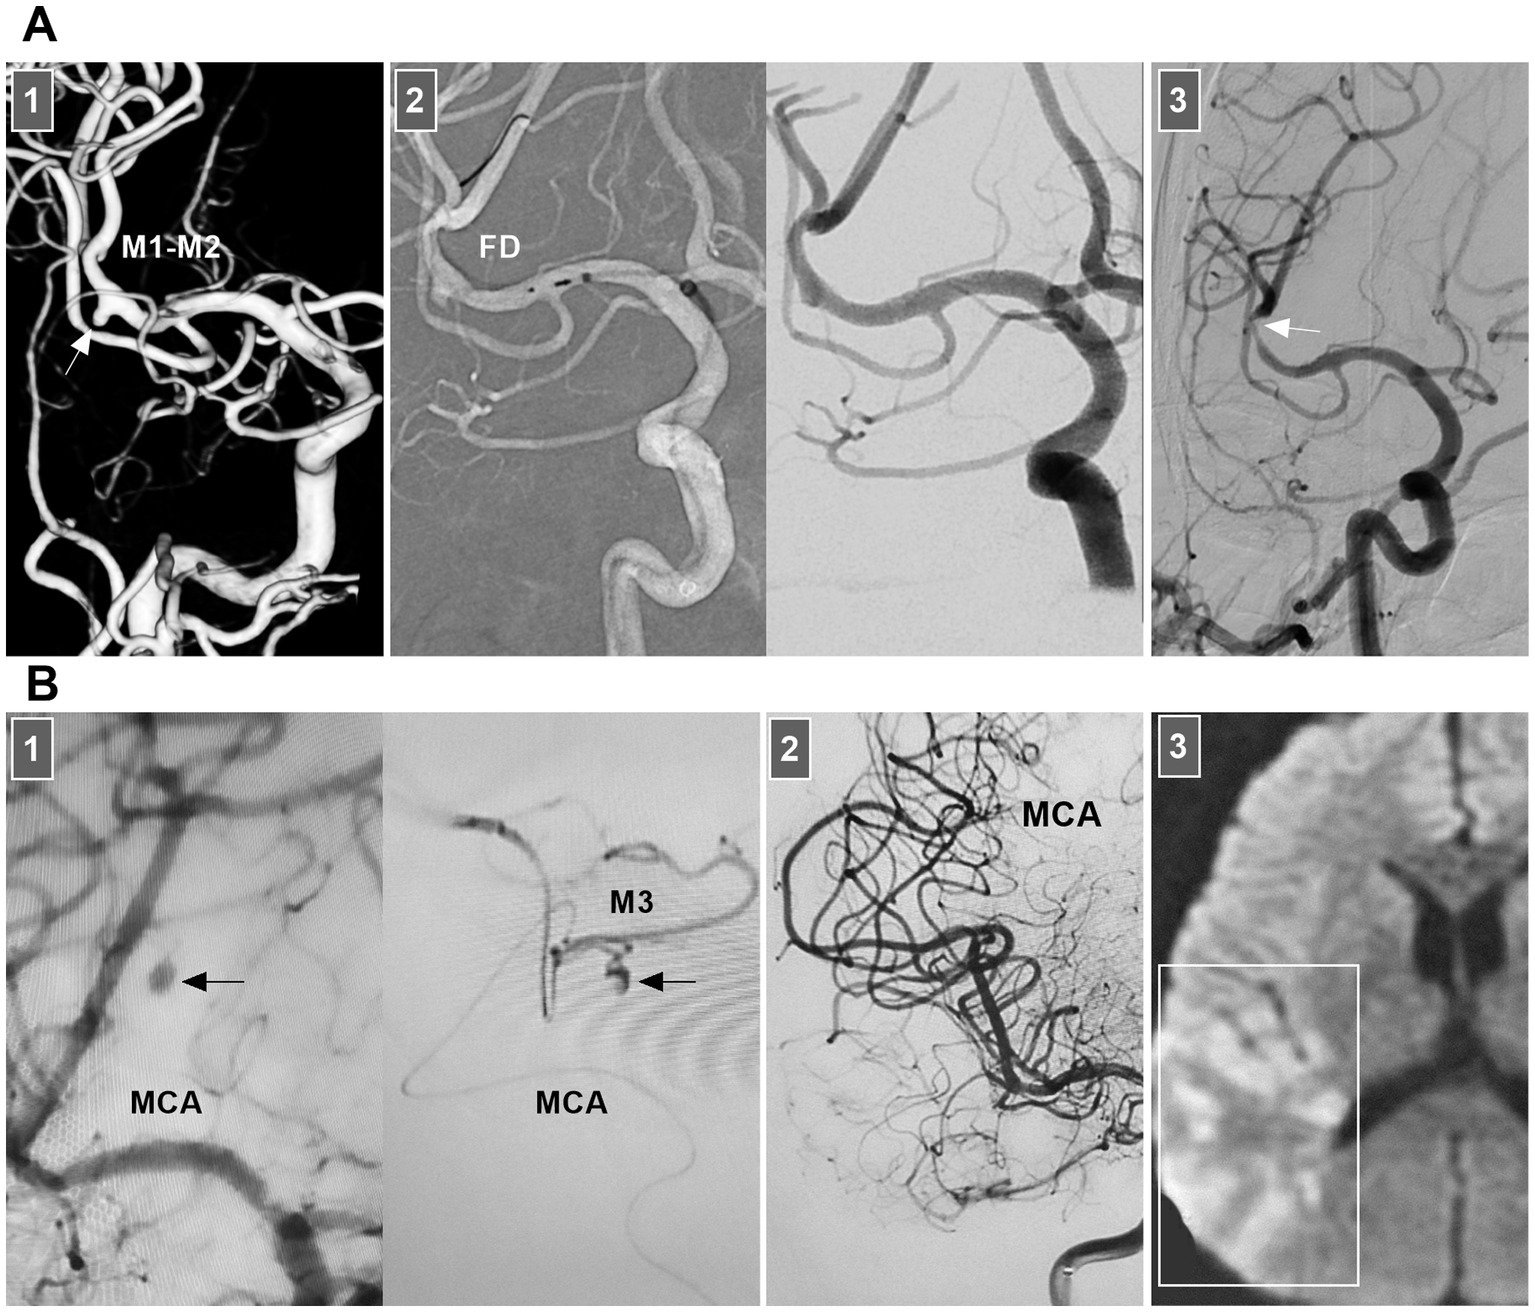

Chronic MCA dissections can present with fusiform or sidewall aneurysmal dilatation. For M1 dissections, FD deployment to reconstruct the M1 segment is an option (Figures 7B,C). For M2 dissections, reconstructive EVT is recommended (Figures 7D,E). However, complications associated with FD deployment must be considered (Figures 6, 8A). If the dissections of the M2 segment of the inferior trunk are giant with thrombi, the distal MCA may experience ischemic preconditioning, and deconstructive EVT is acceptable (57). PAO for M3–M4 dissections can be performed because of adequate leptomeningeal and pial collaterals from the anterior cerebral artery (ACA) and posterior cerebral artery (PCA) (57). In addition, for flow-related distal MCA dissections, deconstructive EVT can be aggressively performed. However, if branches are supplied to important functional areas, such as the central sulcal artery, precentral sulcal artery and postcentral sulcal artery, PAO should be performed cautiously (Figure 8B) (58).

Figure 8

Complication from EVT for MCA dissections. (A) Panel 1: DSA showing a sidewall dissection at M1–M2 junction (arrow). Panel 2: Roadmap image (left panel) and DSA (right panel) showing the dissection was covered by FD. Panel 3: Six-month follow-up DSA showing that the dissection was cured and there was a stenosis of M2 (arrow). (B) Panel 1: DSA (left panel) and microcatheter angiography (right panel) showing a small dissection of M3 (arrows). Panel 2: DSA showing the dissection was embolized by casting liquid embolic agent. Panel 3: Postoperative magnetic resonance image showing that the acute infarction of parietal lobe (frame). DSA, digital subtraction angiography; EVT, endovascular treatment; FD, flow diverter; MCA, middle cerebral artery; M1, first segment of MCA; M2, second segment of MCA; M3, third segment of MCA.

For acute unruptured MCA dissections, even with aneurysm formation, antithrombotic treatment should be prioritized (52, 53). Thrombectomy with/without stenting can be attempted only for acute occluded dissection (54). EVT can be recommended for hemorrhage and confirmed dissecting aneurysms (55). M1 occlusion or isolation of the dissection without efficient bypass poses a significant risk of MCA territory infarct. Although bypass to the distal MCA is often successful, lenticulostriate artery infarction is often inevitable (55). Therefore, preventing rupture and stabilizing the dissected wall while preserving arterial continuity seems to be optimal, allowing subsequent healing via endothelialization.

In selective hemorrhagic MCA dissection without severe stenosis, stent-assisted coiling may be effective (55, 56). For acute dissection, the rupture site is very fragile, and excessive coil packing should be avoided due to the risk of rupture (Figure 6). FDs can decrease blood flow into the rupture site. However, for stenotic MCAs, delivering the FD through a thick microcatheter is often difficult. For hemorrhagic MCA dissection with severe stenosis, conservative treatment had to be the last resort (Figure 7A).

Treatment of MCA dissections. (A) Panel 1: CT showing SAH. Panel 2: DSA images showing a dissection (frames) at MCA trunk with stenosis and dilatation (arrow). Panel 3: Three-month follow-up DSA showing that the dissection (arrow) regressed. (B) Panel 1: DSA (left panel) and X-ray image (right panel) showing a fusiform MCA dissection (arrow) was coiled under the assistance of traditional stenting (asterisks). Panel 2: One-year follow-up DSA showing that the dissecting aneurysm (arrow) was stable and did not grow. Panel 3: Three-year follow-up CT showing fatal intracranial hemorrhage, indicating the dissection ruptured. (C) Panel 1: CT (left panel) showing SAH, DSA (right panel) showing an MCA dissecting aneurysm (arrow). Panel 2: X-ray image showing the FD-assisted coiling. Panel 3: DSA showing that the dissecting aneurysm (arrow) was embolized. (D) Panel 1: DSA (left panel) and X-ray image (right panel) showing a supraclinoid ICA aneurysm was coiled by the assistance of FD deployment (frames), there was a M2 dissection. Panel 2: Roadmap image showing the M2 dissection was stented by LEO baby (long arrow). Panel 3: DSA showing the reconstructed M2 (long arrow). (E) Panel 1: CT angiography showing a M2 dissection. Panel 2: X-ray image showing the dissection was stented by FD deployment (asterisks). Panel 3: DSA (left panel) and its reconstructive image (right panel) of six-month follow-up showing that the M2 segment was reconstructed with less residual dissection (arrows). CT, computed tomography; DSA, digital subtraction angiography; EVT, endovascular treatment; FD, flow diverter; MCA, middle cerebral artery; M2, second segment of MCA; SAH, subarachnoid hemorrhage.